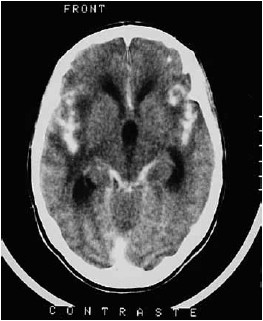

Paciente feminina, 26 anos, admitida no pronto atendimento com relato de cefaleia com piora progressiva na intensidade há 4 semanas, febre aferida de 39 ºC neste mesmo período e, na última semana, sonolência excessiva. Na admissão, você observa a paciente torporosa, localizando estímulos dolorosos nos 4 membros e com rigidez de nuca. Familiares relatam antecedente de uso de drogas. Observe a imagem a seguir.

Com base na história clínica e no exame de imagem, assinale a alternativa que apresenta corretamente, o resultado esperado do exame de líquor desta paciente.